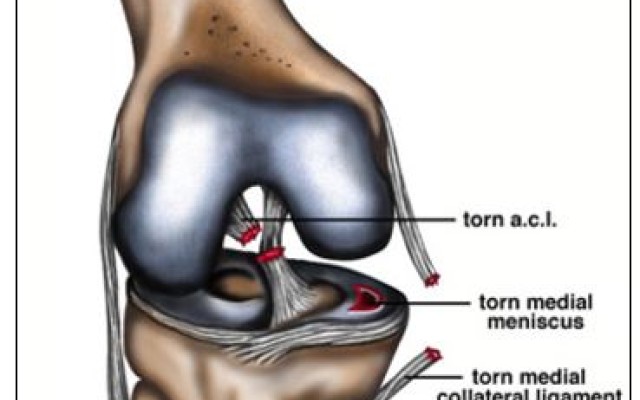

Posted in Dr Kaushik Hazratwala Blogs on Monday, 19 June 2017 by Kaushik Hazratwala

The ACL (anterior cruciate ligament) is part of a complicated network of ligaments that help stabilise and hold the knee. These structures are especially vulnerable to injury during sporting activity or as the result of direct impact. ACL rupture is often associated with meniscal and medial ligament injury. This combination is known as a the “terrible triad” of knee injuries. Knee...Alternate Knee Alignment Technique - Dr Kaushik Hazratwala